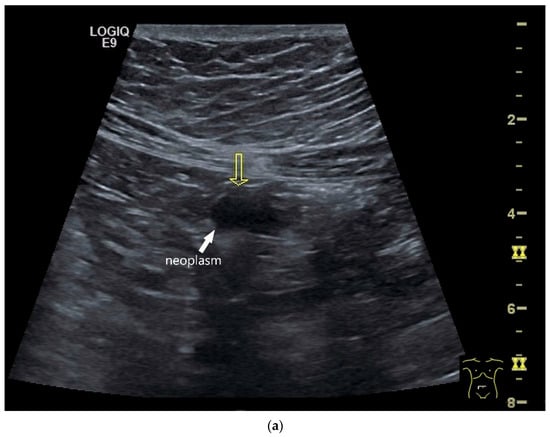

Imaging: Tumors in the jejunum and ileum are usually circular ring-shaped and lumen-stenosing. In the duodenum, about one third have a polypoid component, but a proportion of cases show plaque-like growth [70]. On US, the adenocarcinoma presents as hypoechoic wall thickening with lumen narrowing. The infiltrative wall process may show further tongue-shaped hypoechoic infiltrations into the surrounding tissue. In the case of lymph node involvement, the mesenteric lymph nodes at the level of the tumor may be enlarged and/or morphologically conspicuous [71,72] (Figure 5 and Figure 6).

Figure 6.

Jejunal Adenocarcinoma. Segmental hypoechoic wall thickening (arrows) in the jejunum discovered during anemia diagnostics. Kerckring folds are faintly visible (KF) (a). Adjacent to this is a large round hypoechoic lymph node (L). The surrounding area shows hyperechoic changes (b).

Wu et al. [72] described a single adenocarcinoma in the jejunum using CEUS. The tumor is hypoechoic in B-mode, causing wall thickening and irregular borders. In CEUS, the tumor is hypoenhanced. Wu et al. also performed oral contrast enhancement with UCA [72]. The adenocarcinoma in Crohn’s disease is usually located in the distal jejunum or ileum. It is difficult to distinguish a pathological cockade due to a tumor from a transmural inflammatory wall thickening of Crohn’s disease. For diagnosis, clinical, imaging and laboratory data must be combined with a high degree of experience.